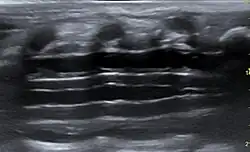

In ausgeprägten Fällen kann man im Röntgenbild eine Aufweitung des Spinalkanales sehen. Die angeborenen Formen können bereits mit einer spinalen Sonographie dargestellt werden.[18][19]